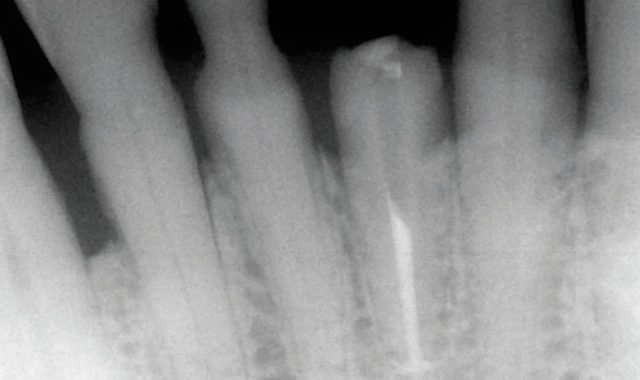

An 88-year-old man presented for restoration of tooth #25, which was fractured and had been endodontically treated (Fig. 1). A thorough intraoral and radiographic examination was performed, which revealed damage to the remaining anterior mandibular teeth incurred over the years as a result of scaling and curettage (Fig. 2). This damage to the

root surface of the lower incisors-which was visible on the radiograph (Fig. 3)-is known as “Riffle-ization.” Described by Dr. Riffle as a technique for removing every last bit of calculus during repeated root scaling, what is now known as “Riffle-izing," ultimately-over the years-changes the shape of the neck of the tooth to resemble an hour glass.